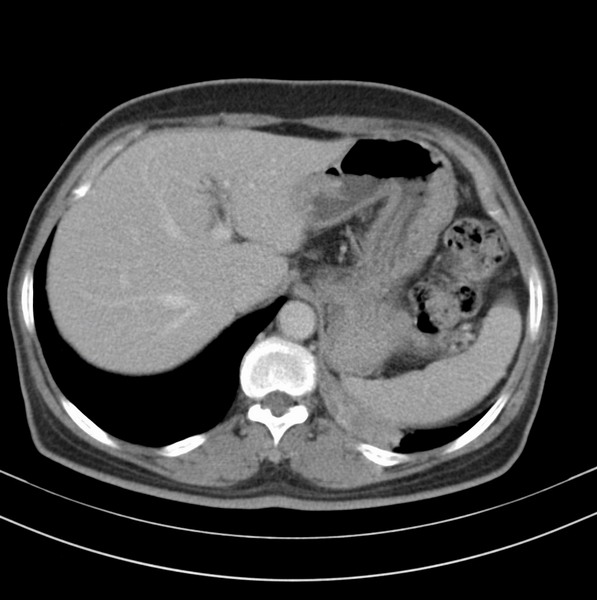

标题: CT20053:胸部增强请会诊。

女、63

咳嗽、胸痛四个月

考虑左下肺中央型肺癌

支持左下中央型肺癌伴阻塞性炎症不张。

包绕左下肺基底段的不规则的软组织肿块,段支气管腔变形、狭窄及阻塞性炎症,病变区不规则强化,又是老年女性支持楼上看法。

考虑左肺下叶中央型肺癌伴阻塞性肺炎、支气管黏液嵌塞。

典型病例:左下肺基底段中央型肺癌,相应支气管狭窄并阻塞性炎症